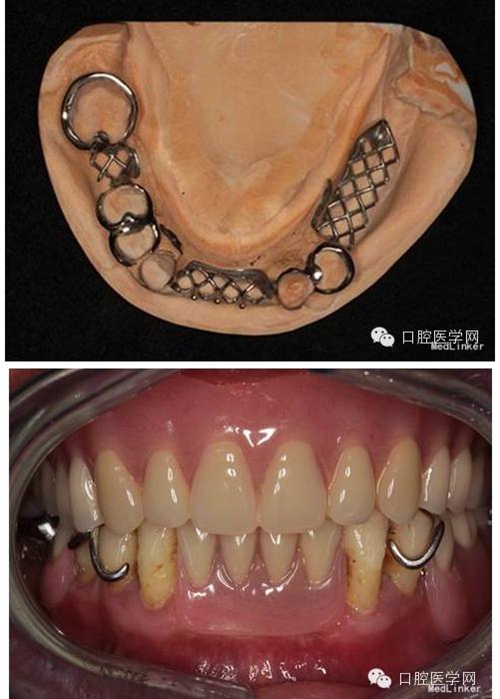

第2次就診:試個(gè)別托盤,磨改邊緣;上頜印模膏邊緣整塑;下頜處理預(yù)留牙,基牙預(yù)備;藻酸鹽取終印模,灌模;上頜制作暫基托,下頜制作鈷鉻合金支架。

第3次就診:試支架;試暫基托;制作蠟堤;記錄垂直距離、水平關(guān)系;轉(zhuǎn)移面弓;比色模型上he架,排牙。

第4次就診:試排牙,充膠第5次就診:初戴義齒,調(diào)he,醫(yī)囑。

本例患者通過系統(tǒng)的檢查發(fā)現(xiàn)#34頸部存在楔狀缺損,予Z350充填治療后再行修復(fù)。#33#43有一定程度的伸長約2mm,有可能會(huì)影響前伸he平衡,但患者強(qiáng)烈拒絕調(diào)磨牙齒,并且考慮到磨改頜面可能造成基牙敏感甚至必要時(shí)需行根管治療等增加治療時(shí)間及治療費(fèi)用,告知患者情況后,患者無法接受,因此未對其進(jìn)行調(diào)磨。人工牙排列時(shí)注意避讓開天然牙,可減小前牙覆he增加覆蓋,以利于獲得前伸he平衡。、